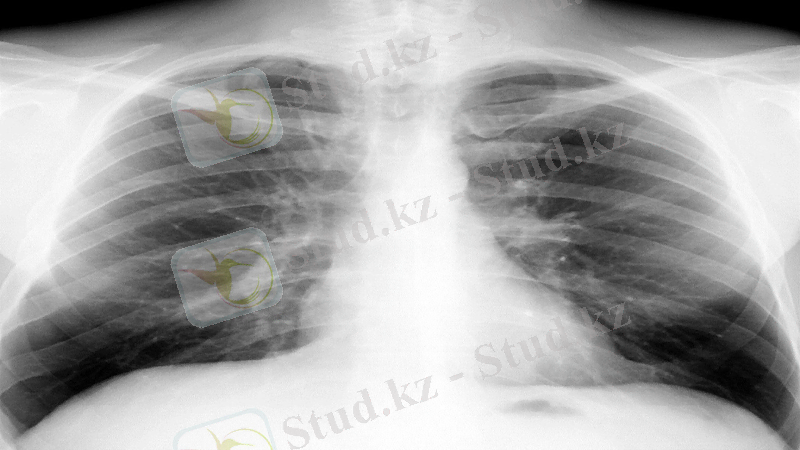

Плевра аурулары жалпы тәжірибеде жиі кездеседі және өкпеге, кеуде қабырғасына, сондай-ақ жүйелік ауруларға әсер ететін негізгі патологиялық жағдайлардың кең ауқымын көрсете алады. Олардың ең көп таралған көрінісі плевра эффузиясының пайда болуында және мұндай науқастардың басым көпшілігінде рентгендік растау және одан әрі тексеру қажет.

Қалыпты плевраның көріністері

Рентгенография кезінде оларға перпендикуляр және қиғаш сәулелену бағытындағы қалыпты плевраның жұқа жапырақшалары ешқандай көлеңке қалдырмайды. Егер плевраның аймақтары сәулелер бойымен едәуір қашықтықта орналасса, онда олар сызықты (жіп тәрізді немесе шаш тәрізді) тығыз көлеңкелер құра алады. Мұндай көлеңкелер көбінесе кеуде қуысының бүйір рентгенограммаларында, көбінесе түзу сызықтарда ортоградтық орналасу учаскелерін анықтайды.